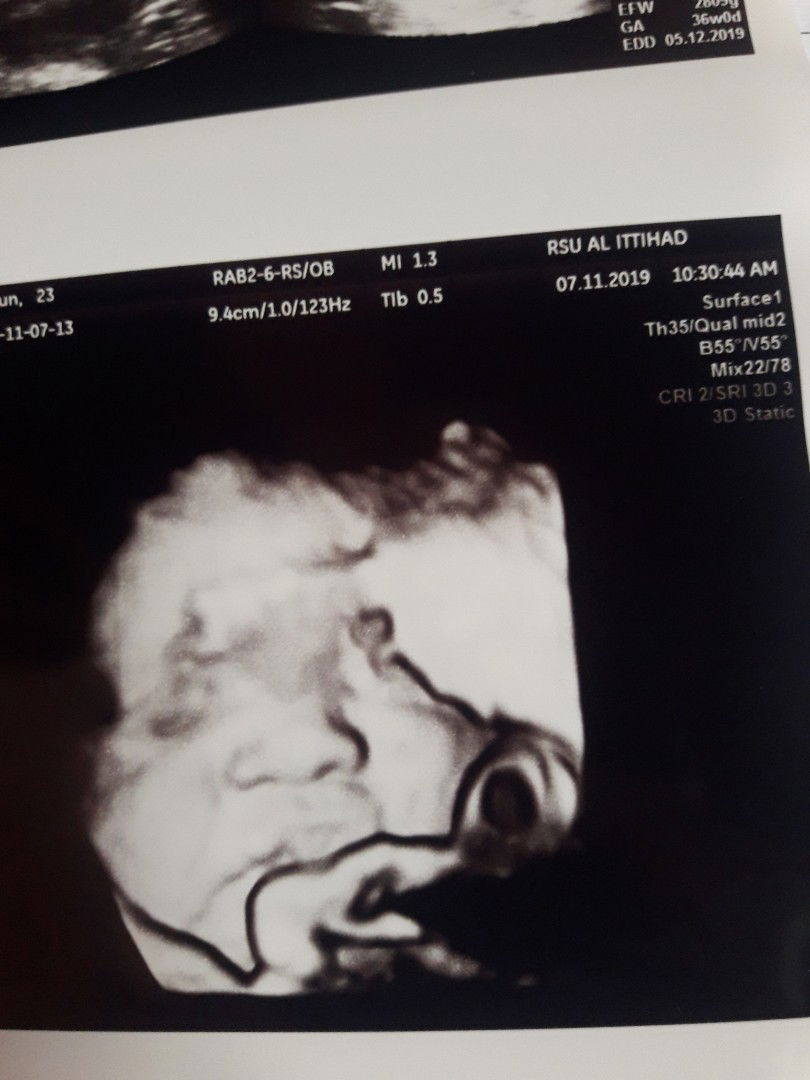

hai bunda... aku lagi hamil, alhamdulillah udah 36w